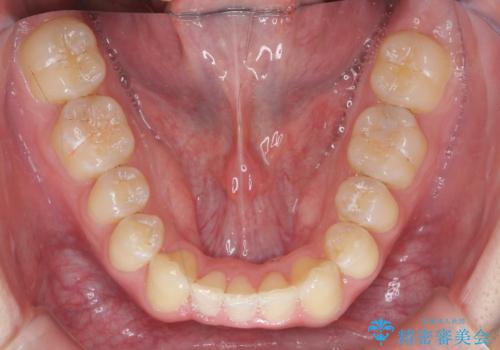

クロスバイト・歯並びが原因の歯肉退縮歯、矯正治療による審美性の改善

- 前歯の歯並び、下顎前歯の歯ぐきの下がり(歯肉退縮)の改善を求めて来院されました。

歯肉退縮の根本的な原因はすれ違った噛み合わせによる為害性のある咬合状態にあるため、歯肉退縮に対し結合組織の移植術を行うのではなく当該歯を抜去し部分矯正を含めた治療計画を立案します。

矯正治療を行ったことで、噛み合わせが安定し審美性も機能性も向上することができました。